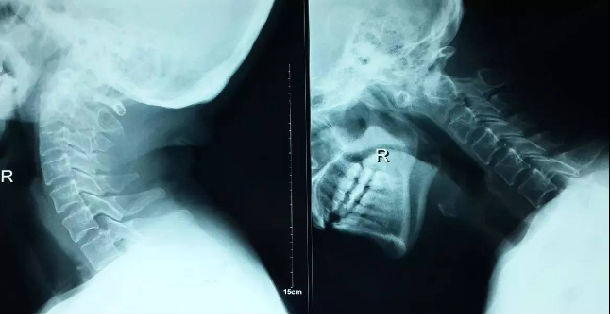

3影像学检查

手术前后伸前屈位X光片寰枢椎脱位为可复性(后伸位脱位复位,前屈位寰齿前间隙(ADl)大于5mm)。寰枢椎CT椎弓根发育良好(大于4mm),磁共振脊髓损伤伴椎管狭窄。

4术前片子